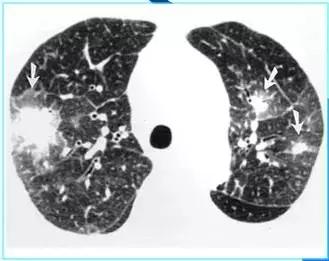

CT征象七:马赛克灌注

马赛克灌注(Mosaicperfusion)

在HRCT上,由于气道疾病或肺血管性疾病引起相邻的肺区血液灌注上的差别而出现的不均匀肺密度区,称马赛克/镶嵌性灌注。常见于造成局部气体滞留或肺实质通气不良疾病中 。

HRCT示略高密度磨玻璃密度影和低密度马赛克灌注区

由于气体储留引起的马赛克灌注

小气道病变引起两侧肺的马赛克灌注

小气道病变引起两侧肺的气体潴留